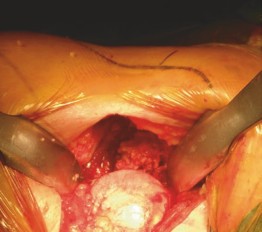

Acetabular Preparation

Exposure of the acetabulum requires precise retractor placement. A curved Mueller or Cobra retractor is placed anteriorly over the anterior wall. A second retractor is placed inferiorly beneath the transverse acetabular ligament to depress the femur posteriorly. A third retractor may be placed superiorly or posteriorly depending on visualization needs.

The labrum is excised, and the cotyloid fossa is cleared of pulvinar to identify the true medial wall. Reaming is performed using offset reamers to avoid impingement on the TFL or ASIS. Fluoroscopy is heavily utilized at this stage to confirm the inclination and anteversion of the reamer and the subsequent acetabular shell. The cup is impacted, and a liner is seated.